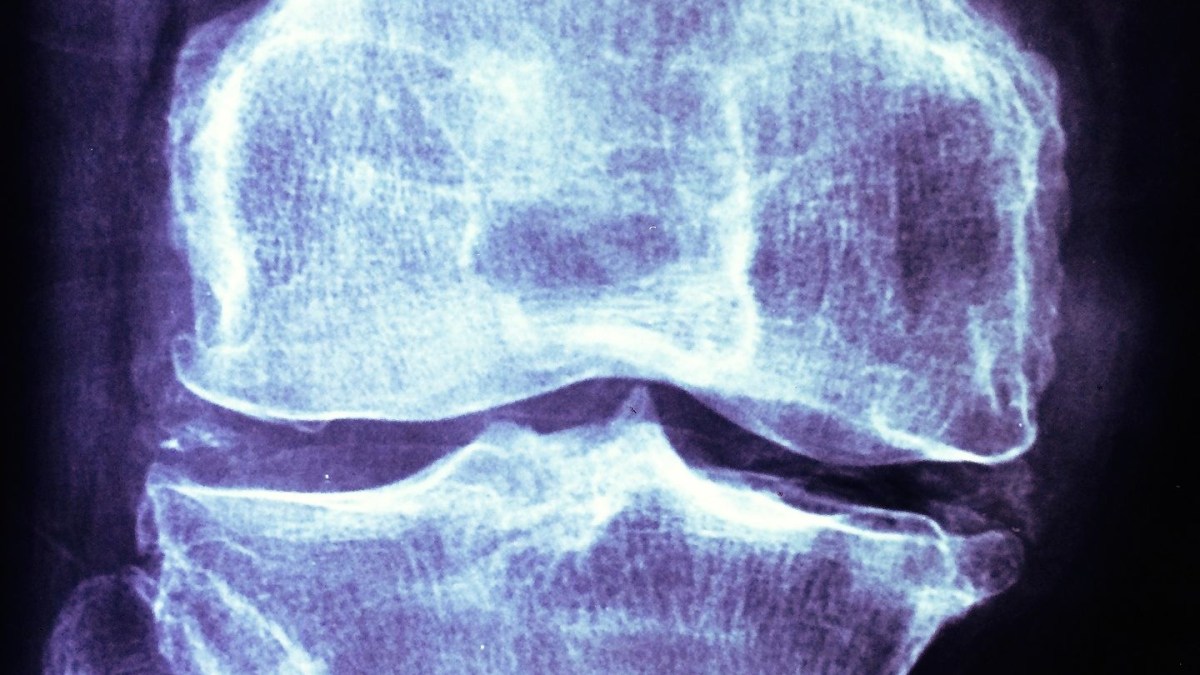

Osteoarthritis, a disease in which cartilage in joints gradually degenerates, currently affects more than 20 million people in the U.S. at an annual cost of about $60 billion. Worse are the costs of arthritis-attributable medical care, which have exceeded $300 billion in recent years. The condition can cause severe pain and impaired ability, and it often leaves people unable to work. But despite its far-reaching impacts, the only treatments currently available for osteoarthritis simply manage pain and symptoms.

The new treatment seeks to change that by delivering an experimental drug directly to the source of the degeneration. The goal was to deliver an experimental drug called insulin-like growth factor 1 (IGF-1) to cells within joints called chondrocytes, which are responsible for producing the cartilage that protects joints.